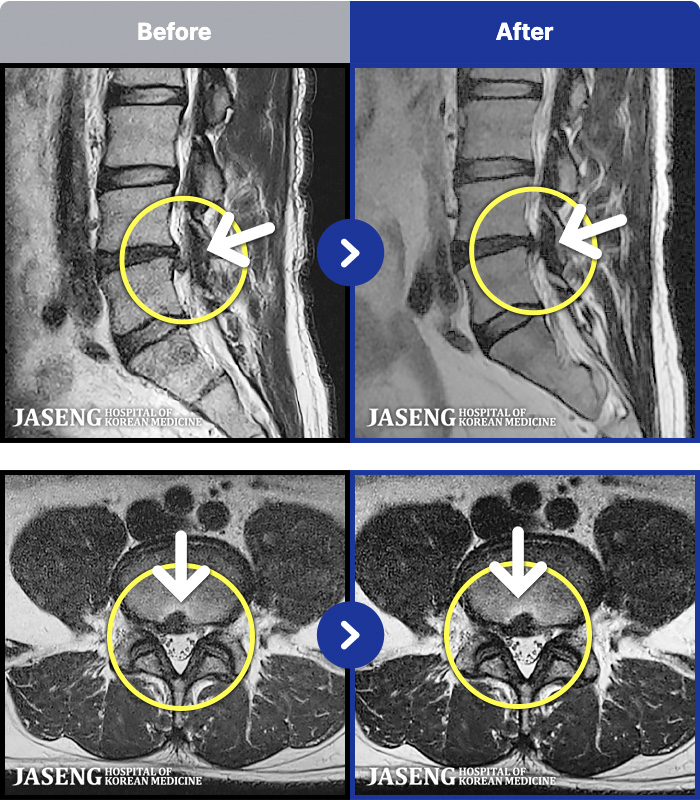

1,257 MRI ũ ʸ Ȯϼ.